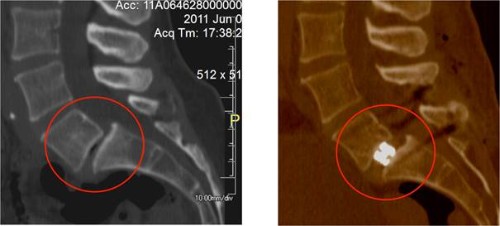

TAC postoperatorio mostrando un disco L5/S1 muy colapsado (izquierda) y con la

altura restaurada tras inserción y expansión del implante expandible (derecha)